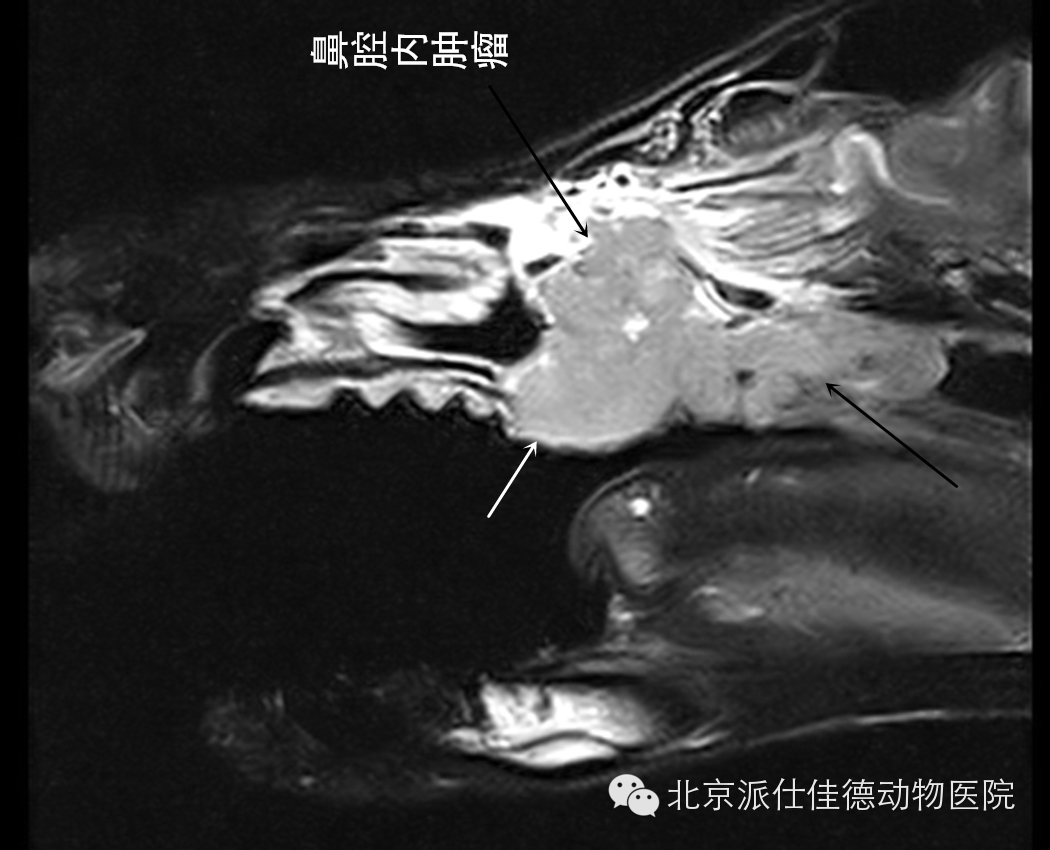

11.有些动物表现为鼻腔流分泌物,刚开始以为是鼻炎或是鼻窦炎,经检查后发现是鼻腔肿瘤。